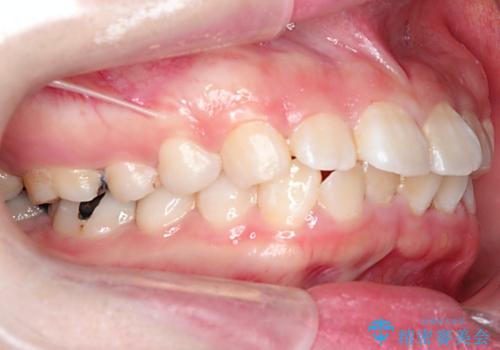

- 口元が出ていることを主訴に来院されました。

上下左右小臼歯を抜歯して審美装置で治療を行いました。

抜歯したスペースをきちんと下げることができるように、矯正用のアンカースクリューを用いて治療をしております。